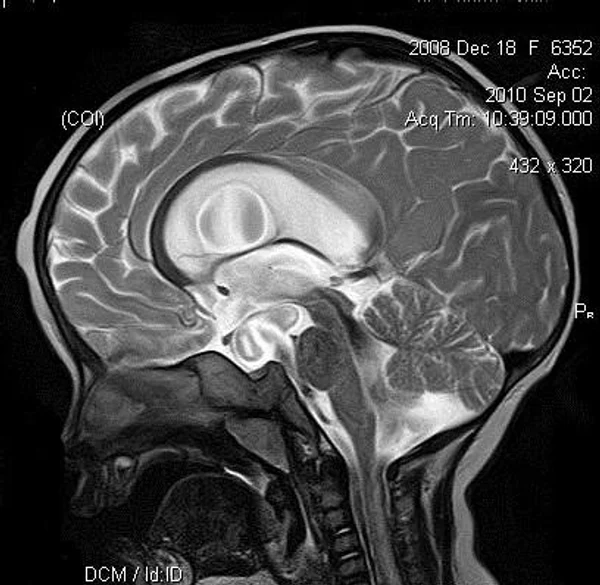

кисты, аномалии Денди-Уокера и др.Операции при внутричерепных кистах. В основном встречаются арахноидальные кисты различных локализаций и кисты сосудистых сплетений боковых желудочков. Пациентам с врождёнными кистами операции проводятся в следующих ситуациях: увеличении объема кисты в динамике, наличии клинических проявлений, компрессии и дислокации мозговых структур, наличии окклюзии ликворных путей. Нами используются 2 способа хирургического лечения кист: эндоскопическая перфорация стенок кист и открытая резекция кист. Открытая резекция кист проводится при ретроцеребеллярных арахноидальных кистах (рис. 2), при арахноидальных кистах межполушарной щели при отсутствии непосредственного контакта их стенок со стенками расширенных желудочков головного мозга и повторного увеличения кист средней черепной ямки после эндоскопической кисто-цистерностомии. Техника операции заключается в проведение краниотомии и максимальном иссечении стенок кист с созданием широкого сообщения кист с субарахноидальным пространством. Эндоскопические операции проводятся при арахноидальных кистах межножковой и пинеальной цистерн, арахноидальных кистах межполушарной щели при тесном контакте их стенок со стенками расширенной желудочковой системы (рис. 3), первично при арахноидальных кистах средней черепной ямки, а также при кистах сосудистых сплетений боковых желудочков. При арахноидальных кистах межножковой цистерны эндоскопически проводится перфорация стенок кисты, сообщая ее с просветом III желудочка и межножковой цистерной – эндоскопическая вентрикуло-кисто-цистерностомия (рис. 4). При арахноидальных кистах пинеальной цистерны проводится перфорация кисты в передне-верхних её отделах с созданием сообщения полости кисты с просветом III желудочка – эндоскопическая кисто-вентрикулостомия. С целью предотвращения облитерации сформированного отверстия иногда в полость кисты под контролем эндоскопа вводится стент перфорированный на протяжении (рис. 5, 6). Эндоскопическая кисто-цистерностомия выполняется при арахноидальных кистах средней черепной ямки. При этом создается широкое сообщение кисты с базальными цистернами. При кистах сосудистых сплетений боковых желудочков проводится их вскрытие в просвет боковых желудочков – эндоскопическая кисто-вентрикулостомия. При множественных кистах проводится их хирургическое сообщение между собой – интеркистосмия